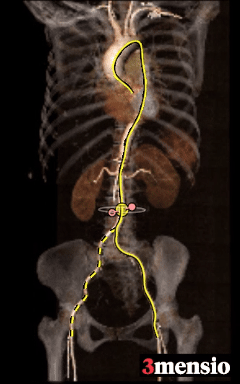

ANNULUS

LVOT

夹角

周75.3mm

周长径24.0mm

周长81.5mm

周长径25.9mm

瓣环水平夹角:44°

STJ

Ascending Aorta

SOV Diameter

高度20.0mm

周长110.5mm

周长径35.2mm

L:33.2 R:29.7 N:31.2

2mm

Super-Annulus

4mm

周长75.5mm

周长73.1mm

周长径23.3mm

周长72.7mm

周长径23.1mm

6mm

8mm

10mm

周长70.4mm

周长径22.4mm

周长68.9mm

周长径21.9mm

周长70.5mm

HU598:1225mm3

HU850:650mm3

LCA Height

12.6mm

RCA Height

17.9mm

LCA & Leaflet

RCA & Leaflet

-

Type1二叶式主动脉瓣(L-R),瓣叶增厚,极重度钙化,主要分布于无冠窦及右冠窦瓣叶,LVOT偏直筒型;

冠脉高度可,瓣叶切线测量距离<冠脉开口上缘到根部距离,结合瓦氏窦及STJ尺寸预估冠脉低风险;

水平夹角36°非横位心,弓角、弓距可,弓部散在钙化,预估输送器可顺利过弓、跨瓣;

外周血管内径、走行可,双侧髂总-腹主动脉见少量钙化斑块,双侧股动脉低分叉。

手术策略制定

此为3例中年龄最大的患者,经术前评估其高龄+Type1型二叶瓣+极重度钙化+不对称分布的特征,TAVR手术操作难度与风险显著升高。为使瓣膜安全精准释放,植入后有效撑开钙化限制,充分展开获得较好的成形,考虑选用国产创新瓣膜ScienCrown系统植入,充分利用其优势设计(直筒型瓣架提供充足的平衡支撑力、100%全释放与全可回收功能确保瓣膜安全精准植入)为TAVR手术保驾护航,为患者带来更优的获益。